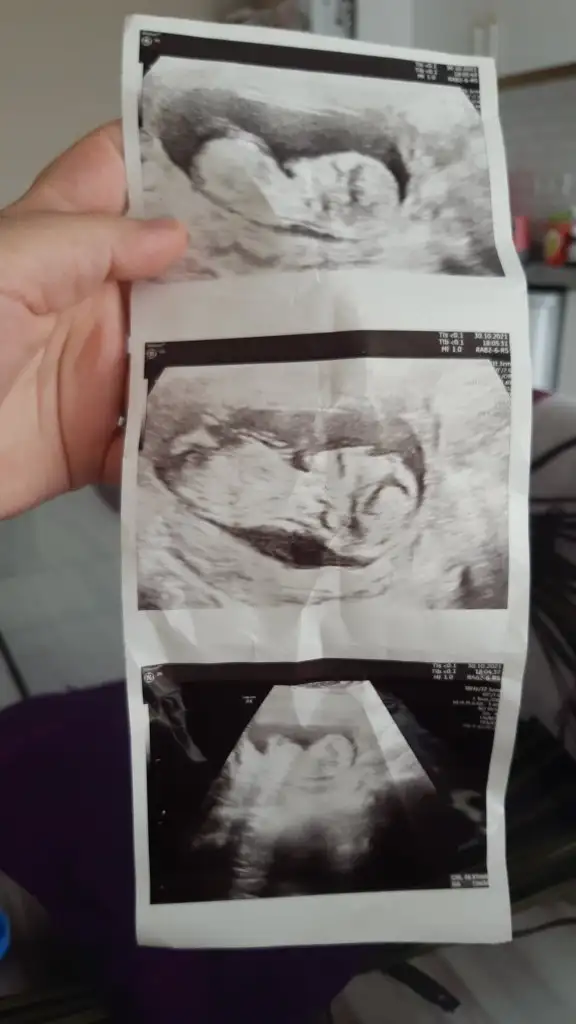

Kız görünüyorIkra meyra canım bana tekrar bakabilir misin erkek demiştin ilk ultrasonlara bana şuan kız gibi geldi ama fikrini merak ediyorum şimdi 13+0 ı payşayım

Erkek görünüyorRica etsem tahminde bulunurmusunuz kndini gostrmedi bebegim snra doktor bakti kordon vardı 13+3gunluk ultrason resmi Eki Görüntüle 2951968

Teşekkür ederim canımm sonucu söylerim 3 hafta sonraKız görünüyor

Emin olamadım kız gibi sanki12+2 banada yorum yaparmisinIkra meyra

Bu haftalarda nub olmaz cnm 11 12 13 haftalar olmalı şekli kıza benzetimMerhabalar herkes sizi öneriyor bana da bir tanminde bulunur musunuz tam 14 haftalık ama kordon girdiği için emin olmamakla beraber erkek dendi içimden hep kız geçiyor rüya test vs ile cuma kesinleşecek ama sizden tahmin etmenizi istiyorum yardımcı olur musunuz